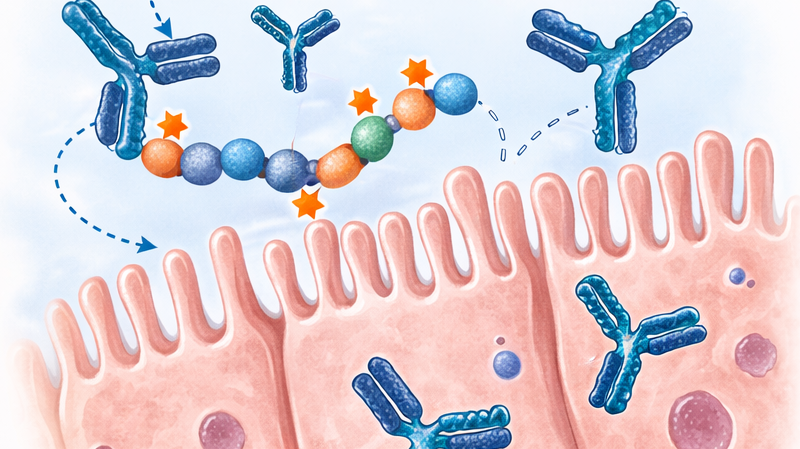

Utilidad clínica y diagnóstica de anti-DGP en EC

La enfermedad celíaca (EC) es una enteropatía autoinmune ...